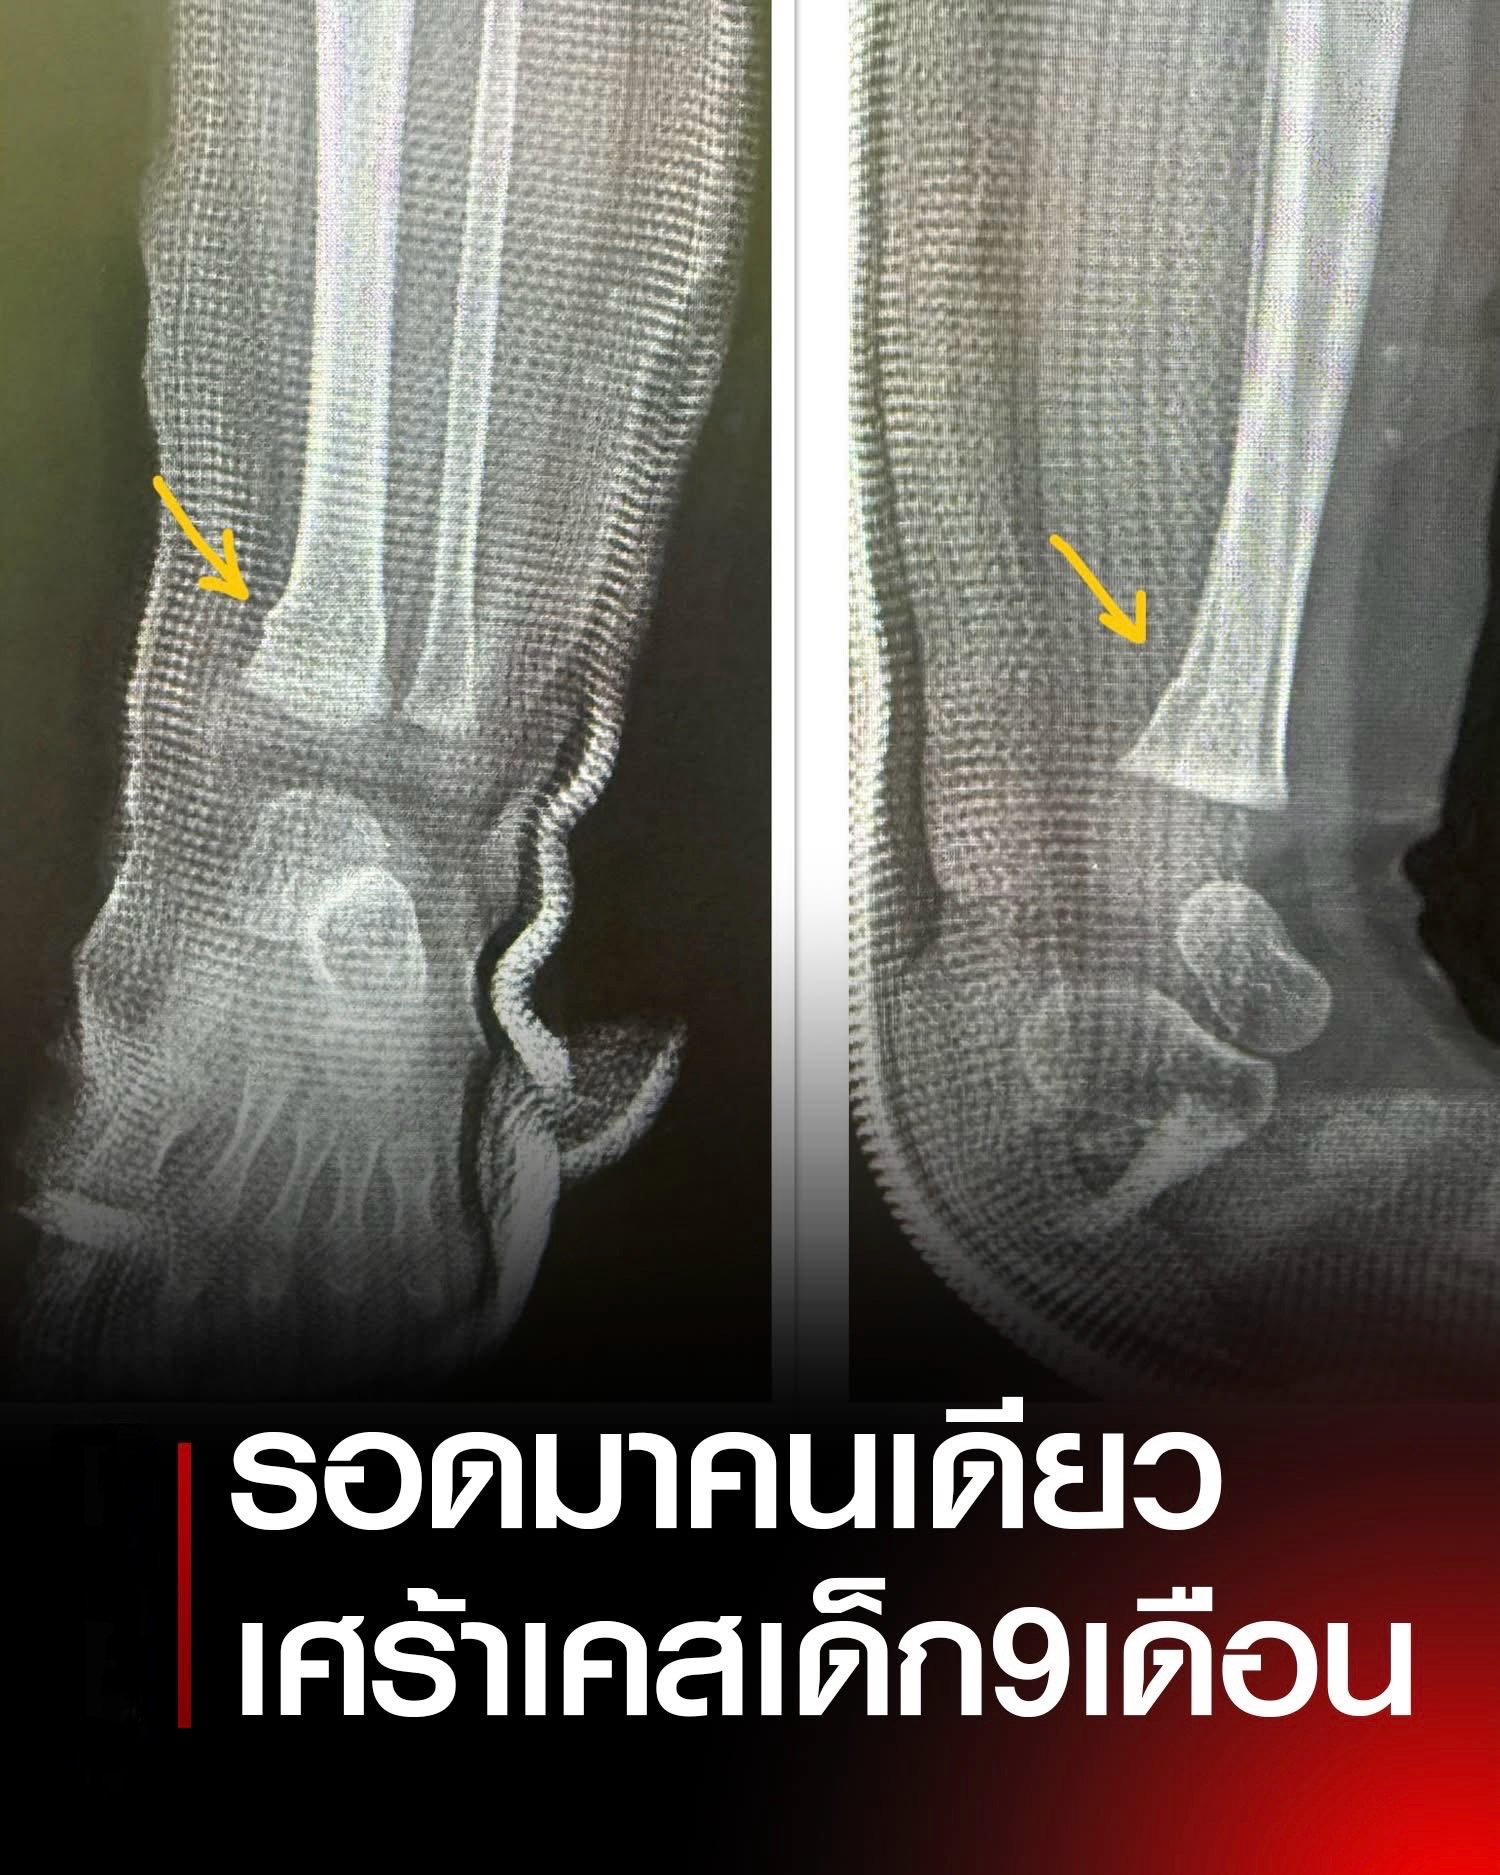

หมอเล่าสะเทือนใจ เด็ก 9 เดือน นอนไอซียู จากอุบัติเหตุ ถามถึงพ่อแม่จุกอก เสียหมดรวมทั้งยาย.